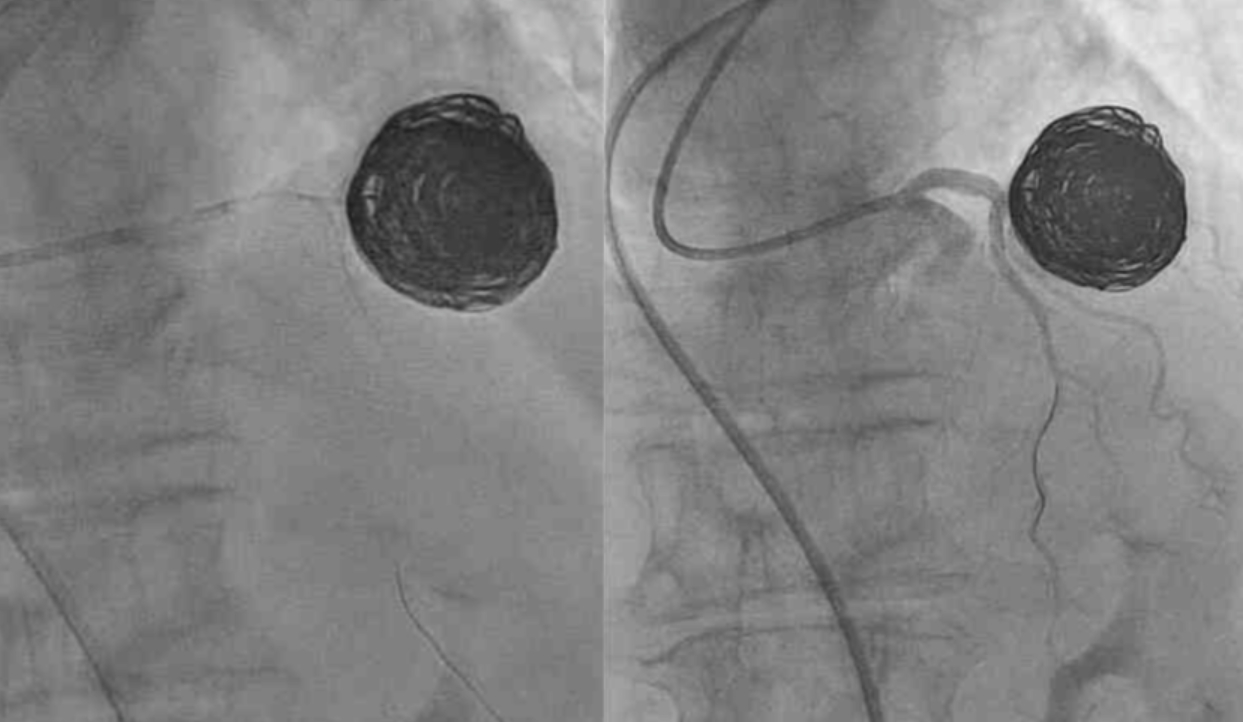

A 78-year female with a history of hypertension, hyperlipidemia, HIV, and rheumatoid arthritis presented with atypical chest pain. Coronary CTA was performed, revealing an incidental calcified saccular aneurysm, with a size of 33.9 x 33.4 mm, arising from the distal LMCA with intra-aneurysmal calcifications and thrombus (Figure 1). The aneurysm caused mild luminal compression of the proximal LAD (p-LAD). Coronary arteries were non-obstructive. Invasive coronary angiogram was done and the patient underwent coiling embolization to exclude the aneurysm with no periprocedural complications (Figure 2). The patient tolerated the procedure and is planned to have both clinical and non-invasive imaging follow-up. In this patient, CTA enabled prompt diagnosis and guided further intervention.